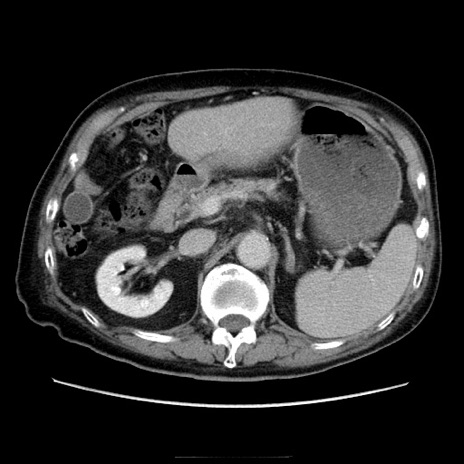

症例21(横断像)

【症例】70歳代男性

【主訴】腹痛

【現病歴】肝硬変・肝細胞癌にてかかりつけの方。約9時間前に食後より腹痛出現。症状が徐々に増悪し、嘔吐出現したため来院。

【既往歴】肝硬変、肝細胞癌(RFA、TACE後)

【身体所見】意識清明、表情苦悶様、BT 36℃、BP 129/78mmHg、P 88bpm、SpO2 97%(RA)、右上腹部から心窩部にかけて圧痛あり、反跳痛なし、筋性防御あり。

【データ】WBC 5800、CRP 0.16